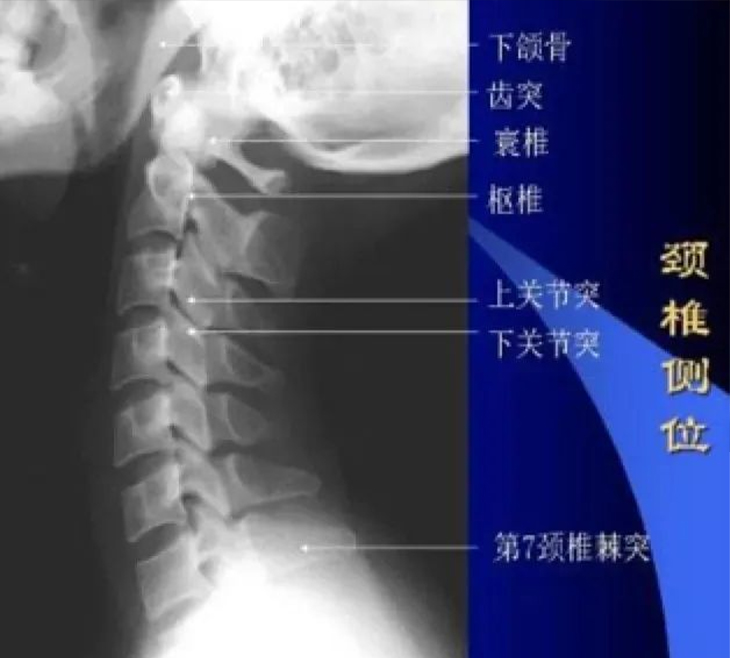

它是精确定位在第七节颈椎以及上段胸椎处的一个软组织脂肪化、增生的现象。常见于女性、久坐办公人群、低头族和老年人。颈后大包其实是一个不良姿势体态形成的结果。伴随着这个结果,还有很多其他的症状,如头晕、头疼、耳鸣、颈部肌肉张力高而导致的头颈活动度减少等一系列问题,甚至腰椎、骨盆、下肢的问题都与颈后大包有密切关系。为什么这么说呢?让我们来仔细看看颈胸交界处的解剖分析。

为了让大家更清晰地理解颈后大包的成因,我们将脊柱简单地比作一辆火车,火车的每一节就相当于我们脊柱的每一节椎体。对脊柱这辆“火车”而言,有三条主要的运动轨道,即矢状面的屈伸运动轨道、冠状面侧屈运动轨道和水平面的旋转运动轨道。单从骨骼结构上看,我们的第七颈椎较适合做屈伸和侧屈的关节运动,旋转的关节运动很少,而胸椎是适合旋转的关节运动。从骨骼结构的角度看「颈后大包」,它确实处在人体脊柱结构功能上过渡、应力相对集中的区域,这里较容易出现问题。我们再来仔细看看椎体间关节突关节。如果“车厢”间连接情况不太好,也就是说第七颈椎与相邻椎体存在对位不正的话,脊柱这辆“火车”在任何一条轨道上行驶运动时都会阻碍重重。